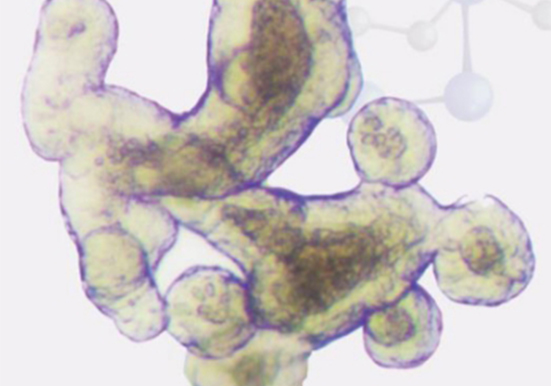

类器官明场图片展示